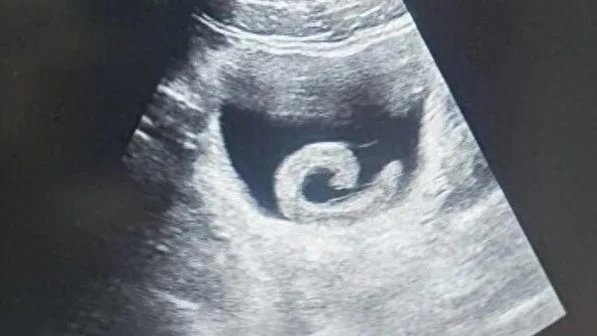

Hình ảnh siêu âm cho thấy một con đỉa sống trongbàng quang của người đàn ông ở Trịnh Châu, Trung Quốc, trước khi được các bác sĩ tiến hành phẫu thuật lấy ra. Ảnh: O.C

Con đỉa đã gây ra cho Zheng những cơn đau dữ dội đến mức anh không còn lựa chọn nào khác ngoài việc đến phòng cấp cứu của một bệnh viện địa phương. Khi nghe lý do, các bác sĩ không khỏi sửng sốt. Kết quả siêu âm xác nhận đúng như anh trình bày: một con đỉa sống đang ở trong bàng quang. Ngay lập tức, các bác sĩ chuẩn bị cho ca phẫu thuật khẩn cấp nhằm loại bỏ ký sinh trùng và cứu mạng bệnh nhân.